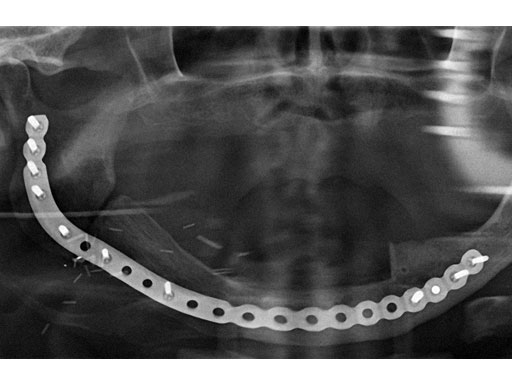

Case 2: A 65-year-old man suffering from an oral cancer in the anterolateral floor of the mouth with infiltration of the right mandible. The preformed reconstruction plate was applied to the lateral surface of the hemimandible prior to en bloc tumor resection, including a bone segment via extended submandibular access. The missing bone was replaced with a revascularized scapula border in combination with a soft-tissue parascapular flap. The patient has had no recurrence 1.5 years postoperatively.

Fig 6 Panoramic x-ray 1.5 years postoperatively.

Case provided by Carl-Peter Cornelius, Mnchen, Germany